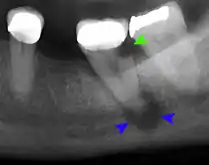

Lateral periodontal abscess (blue arrows) due to a fracture (green arrows)

A periodontal abscess (lateral abscess) is a collection of pus that forms in the gingival crevices, usually as a result of chronic periodontitis where the pockets are pathologically deepened greater than 3mm. A healthy gingival pocket will contain bacteria and some calculus kept in check by the immune system. As the pocket deepens, the balance is disrupted, and an acute inflammatory response results, forming pus. The debris and swelling then disrupt the normal flow of fluids into and out of the pocket, rapidly accelerating the inflammatory cycle. Larger pockets also have a greater likelihood of collecting food debris, creating additional sources of infection.[21]:443

Periodontal abscesses are less common than apical abscesses, but are still frequent. The key difference between the two is that the pulp of the tooth tends to be alive, and will respond normally to pulp tests. However, an untreated periodontal abscess may still cause the pulp to die if it reaches the tooth apex in a periodontic-endodontic lesion. A periodontal abscess can occur as the result of tooth fracture, food packing into a periodontal pocket (with poorly shaped fillings), calculus build-up, and lowered immune responses (such as in diabetes). Periodontal abscess can also occur after periodontal scaling, which causes the gums to tighten around the teeth and trap debris in the pocket.[21]:444–445 Toothache caused by a periodontal abscess is generally deep and throbbing. The oral mucosa covering an early periodontal abscess appears erythematous (red), swollen, shiny, and painful to touch.[22]